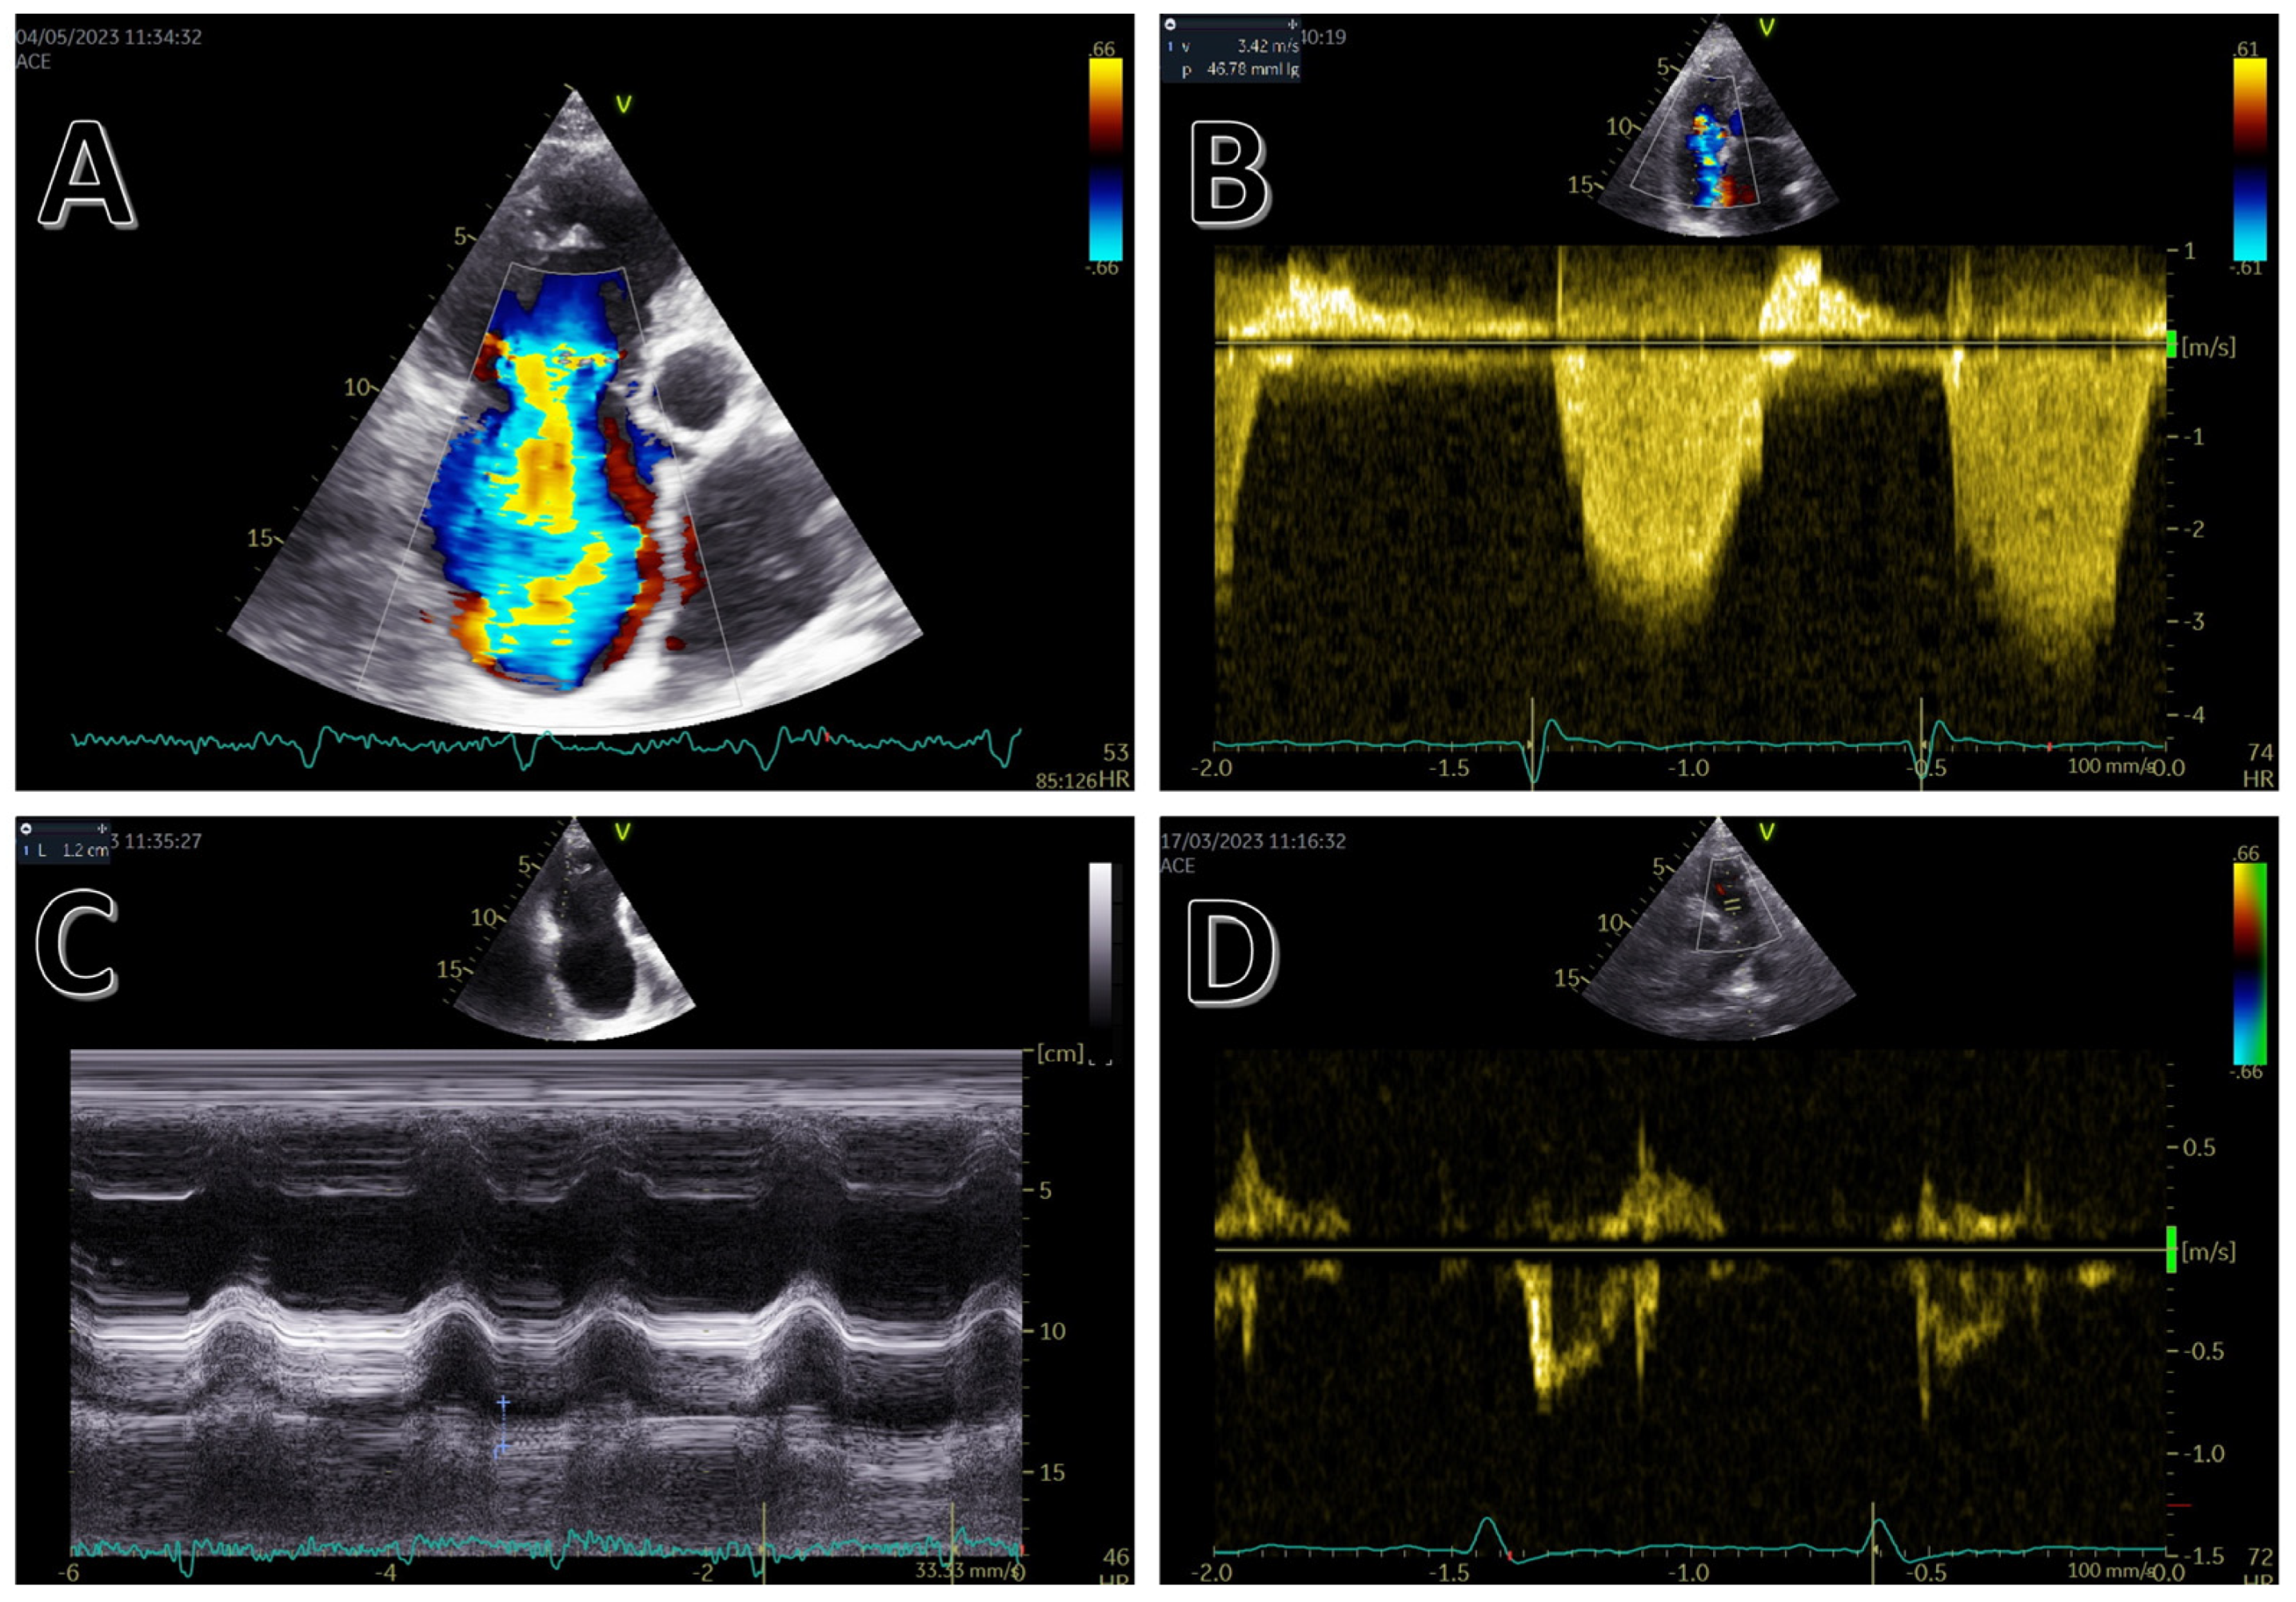

3. Echocardiography